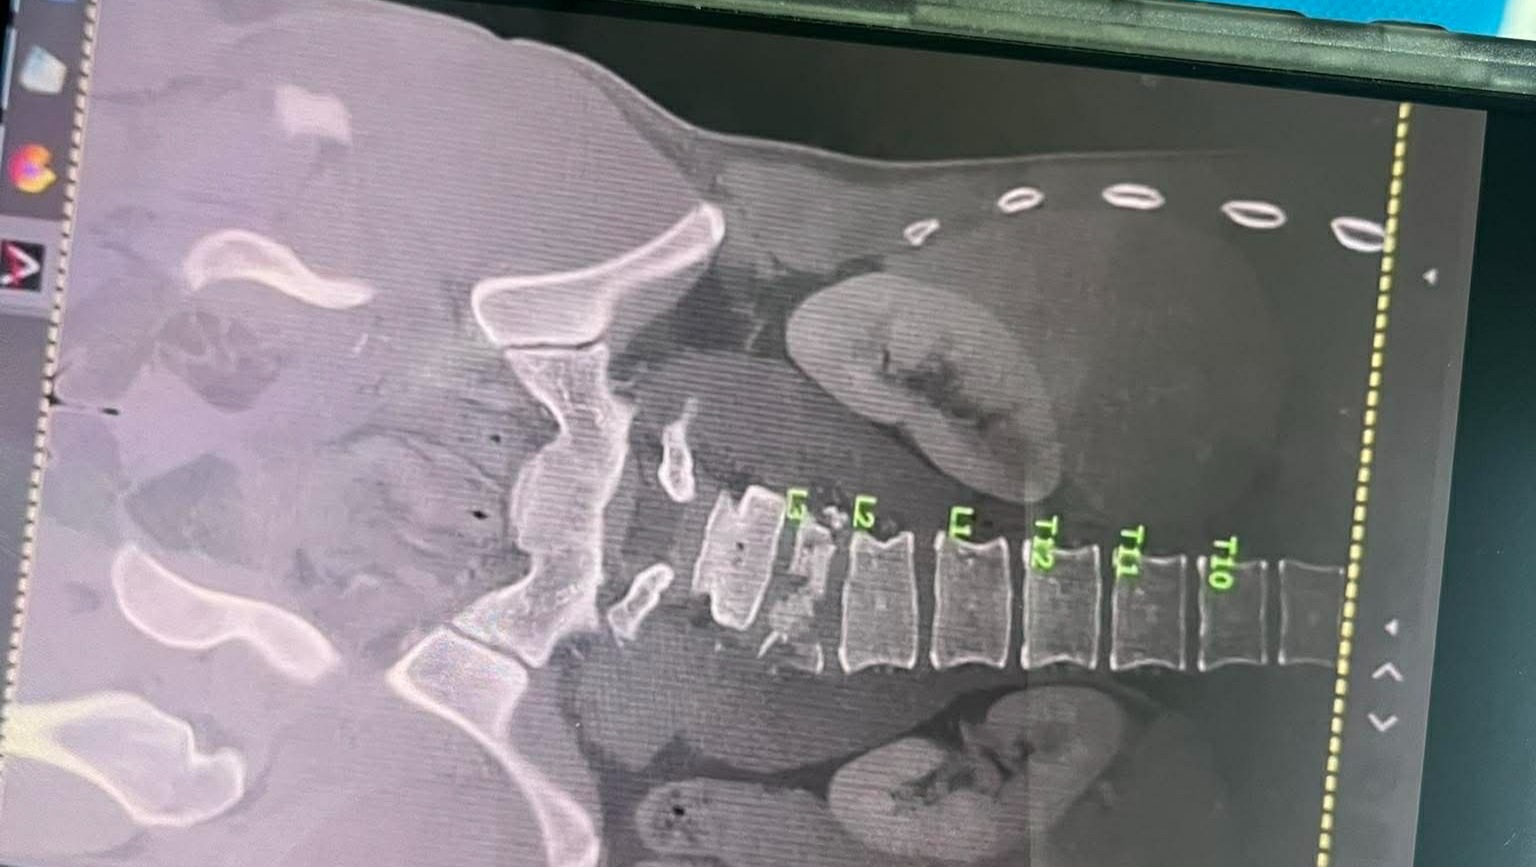

Koby is currently in a Thai hospital facing multiple complex surgeries. The first will be a major spinal operation involving the fusion of his L1–L5 vertebrae. He also has a bleed on his brain and liver, along with further damage to his kidneys and bladder. His condition is serious, and the medical team is working around the clock to stabilise him and prepare him for the surgeries ahead.